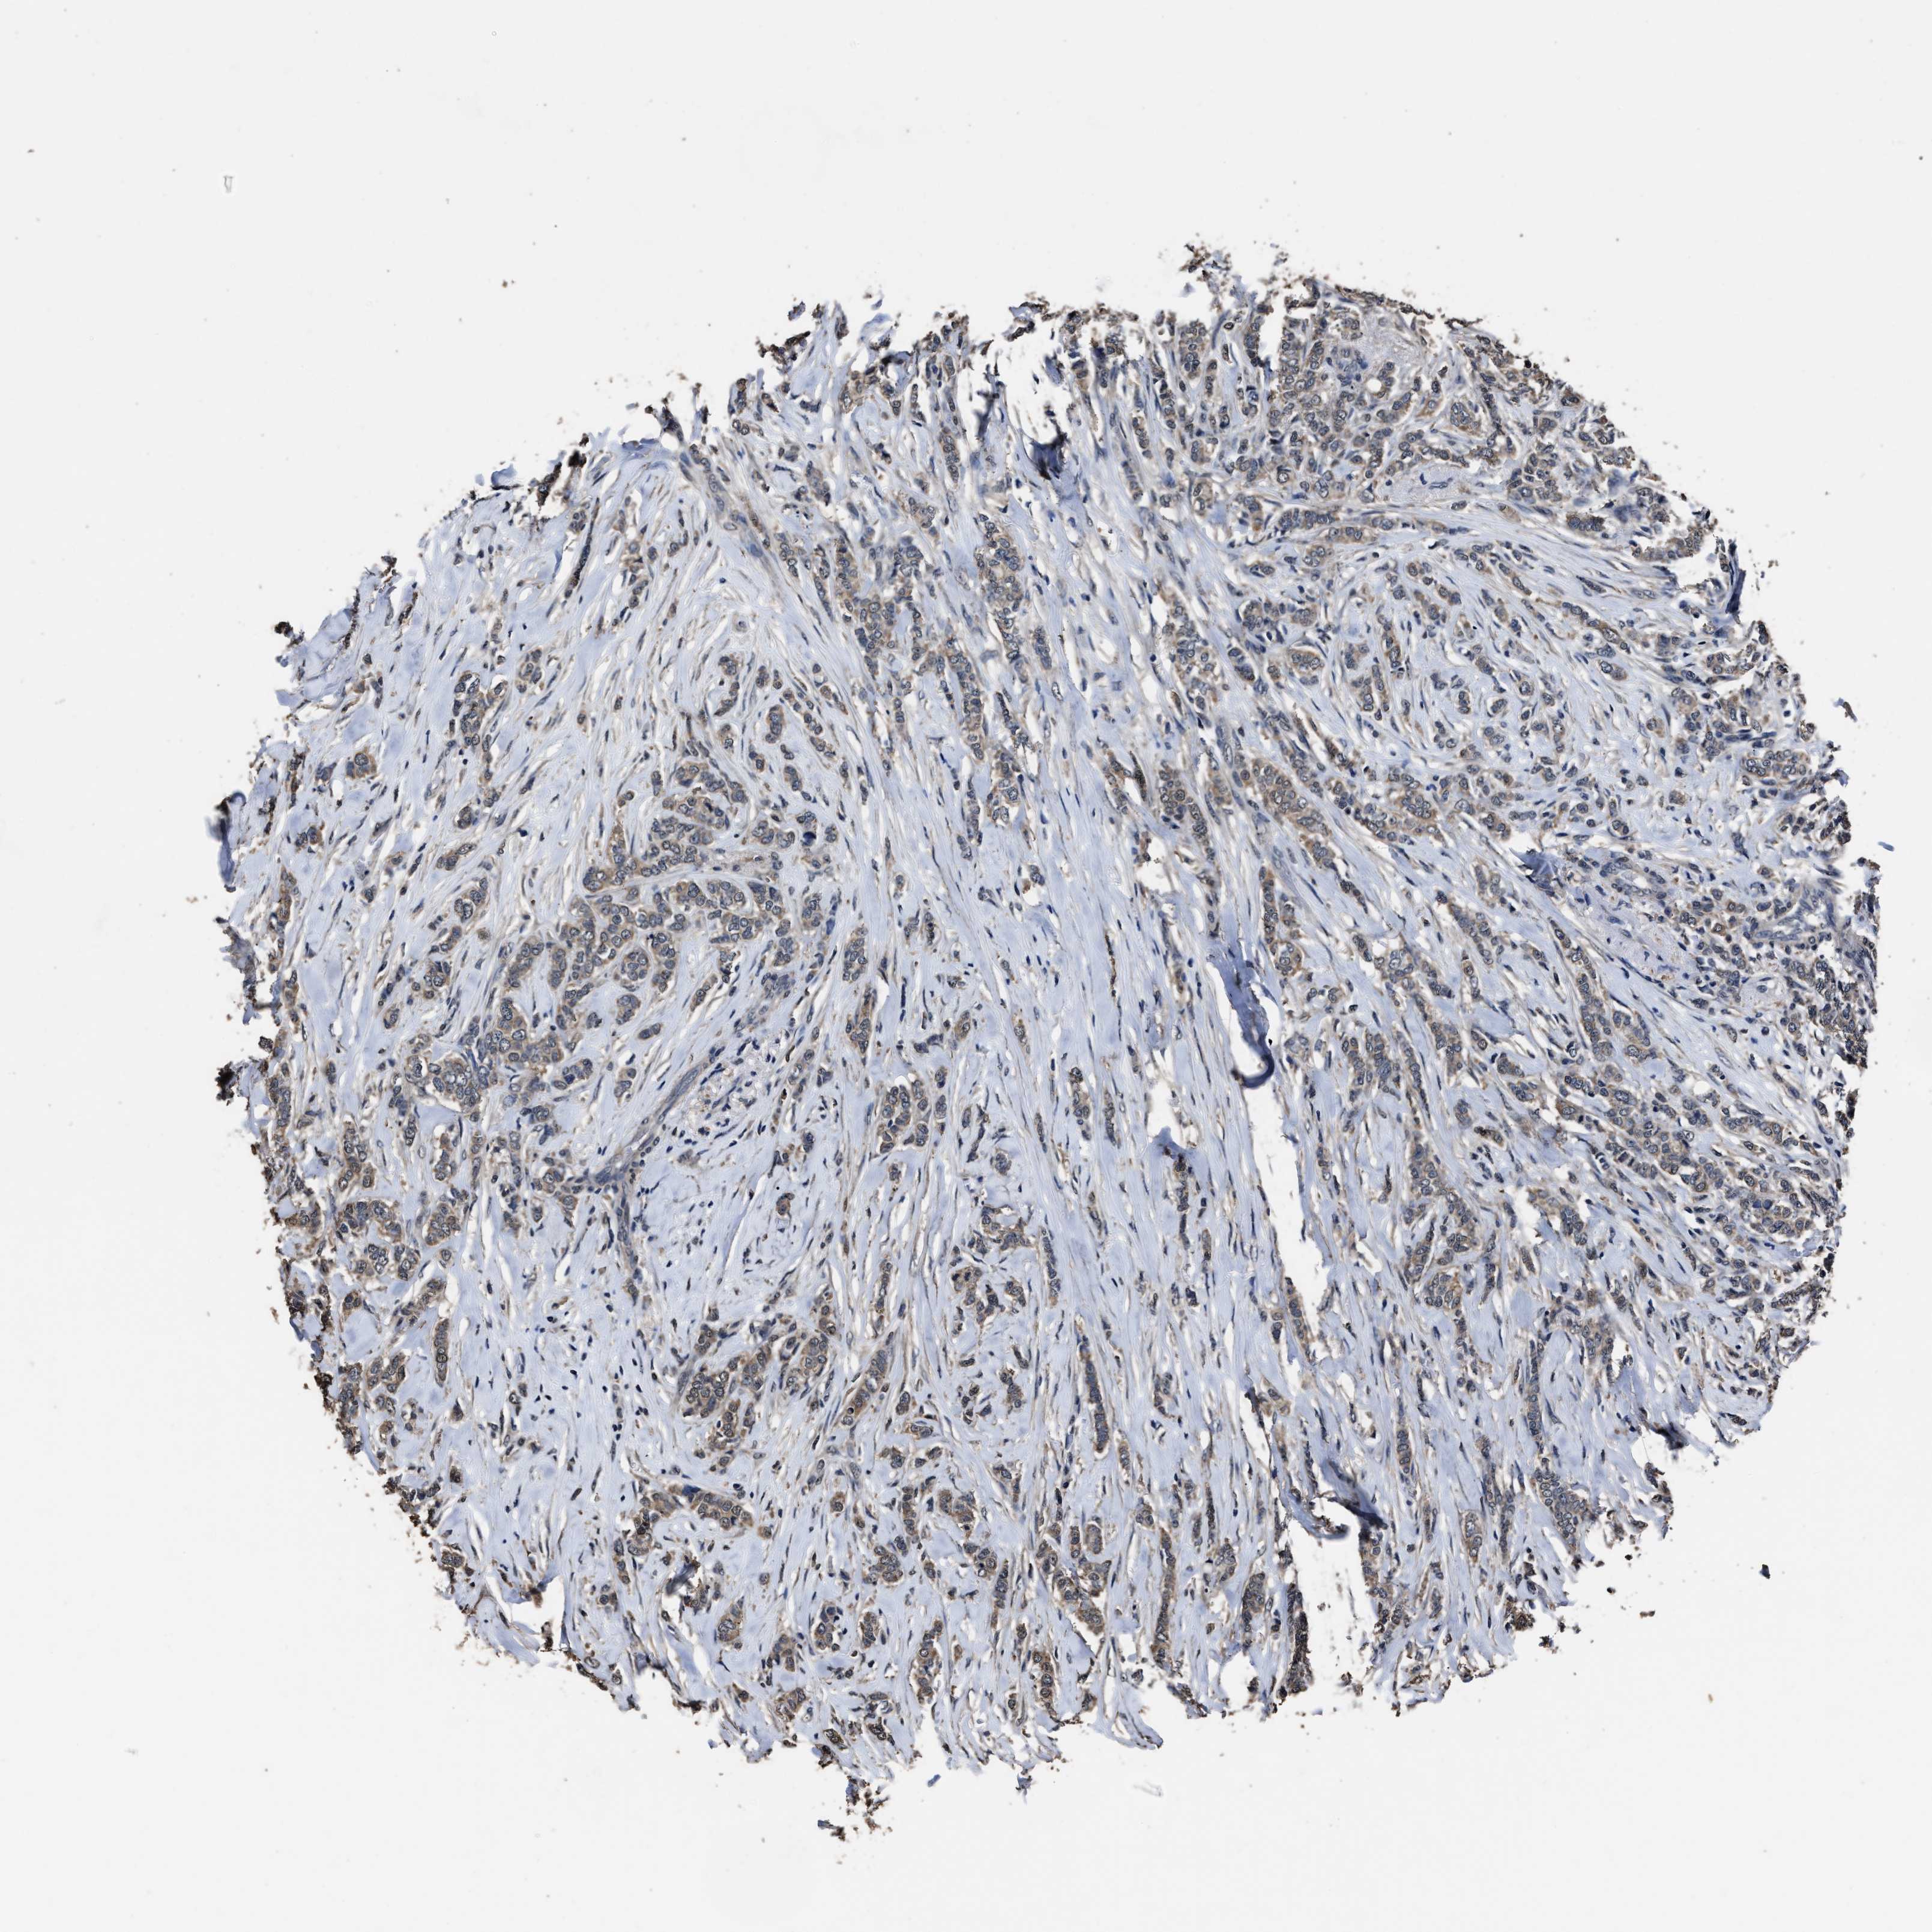

CANCER BREAST CANCER Show tissue menu

BRCA TCGA BRCA VALIDATION PROTEIN EXPRESSION